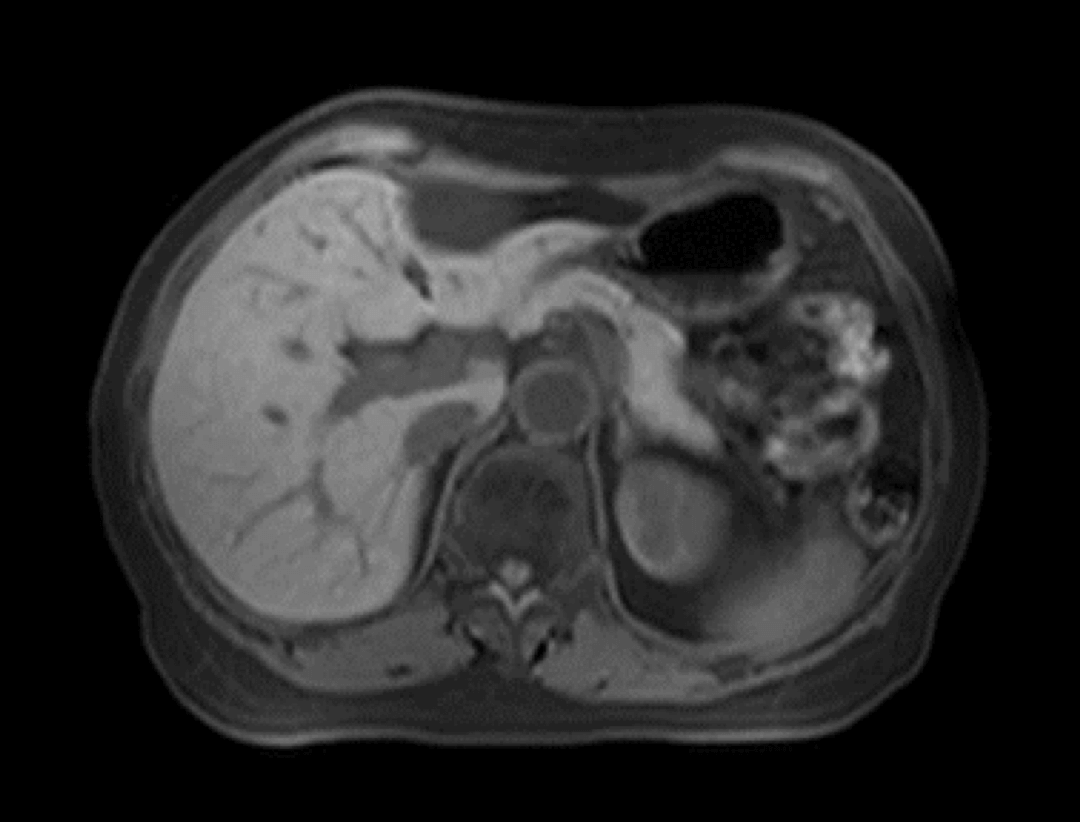

uCS® imaging is applied to the MRI abdominal dynamic scanning enhancement, which can achieve 16× acquisition acceleration and clearly capture the continuous dynamic changes of tissue signals.

Abdomen